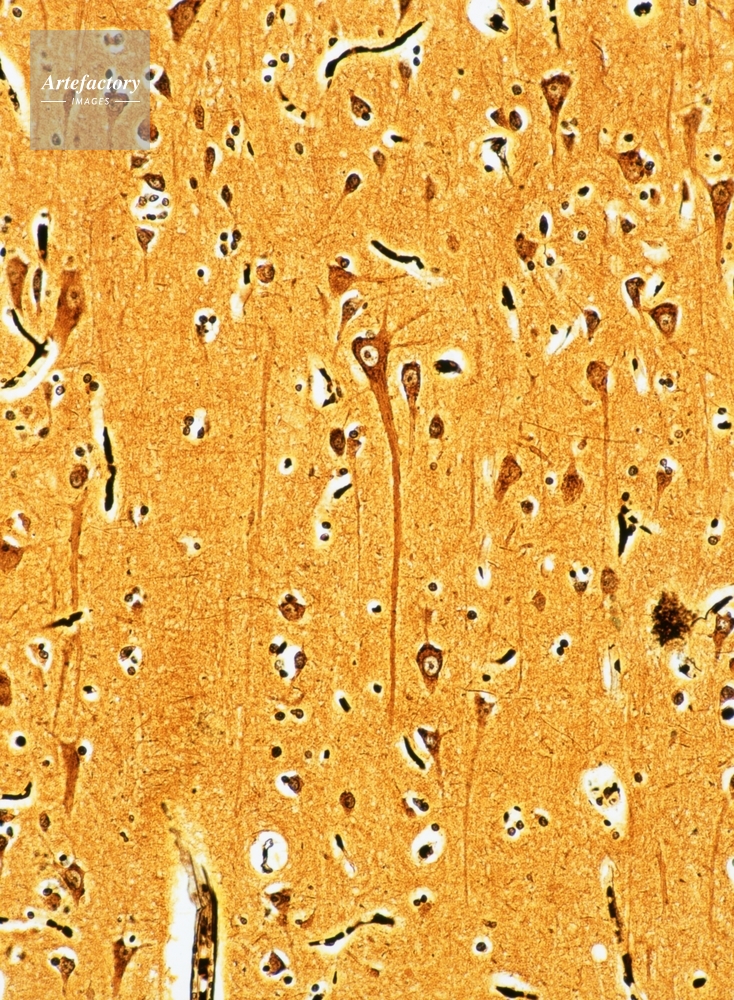

| 作品タイトル | 大脳皮質の神経細胞(人) | モデルリリース | なし | |

| キャプション | 銀染色。長辺55㎜の場合、顕微鏡倍率160倍。 | 制限事項 | ||